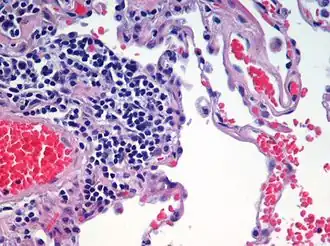

Alveoli

Alveoli consist of two types of alveolar cell and an alveolar macrophage. The two types of cell are known as type I and type II cells[32] (also known as pneumocytes).[3] Types I and II make up the walls and alveolar septa. Type I cells provide 95% of the surface area of each alveoli and are flat ("squamous"), and Type II cells generally cluster in the corners of the alveoli and have a cuboidal shape.[33] Despite this, cells occur in a roughly equal ratio of 1:1 or 6:4.[32][33]

Type I are squamous epithelial cells that make up the alveolar wall structure. They have extremely thin walls that enable an easy gas exchange.[32] These type I cells also make up the alveolar septa which separate each alveolus. The septa consist of an epithelial lining and associated basement membranes.[33] Type I cells are not able to divide, and consequently rely on differentiation from Type II cells.[33]

Type II are larger and they line the alveoli and produce and secrete epithelial lining fluid, and lung surfactant.[34][32] Type II cells are able to divide and differentiate to Type I cells.[33]

The alveolar macrophages have an important role in the immune system. They remove substances which deposit in the alveoli including loose red blood cells that have been forced out from blood vessels.[33]